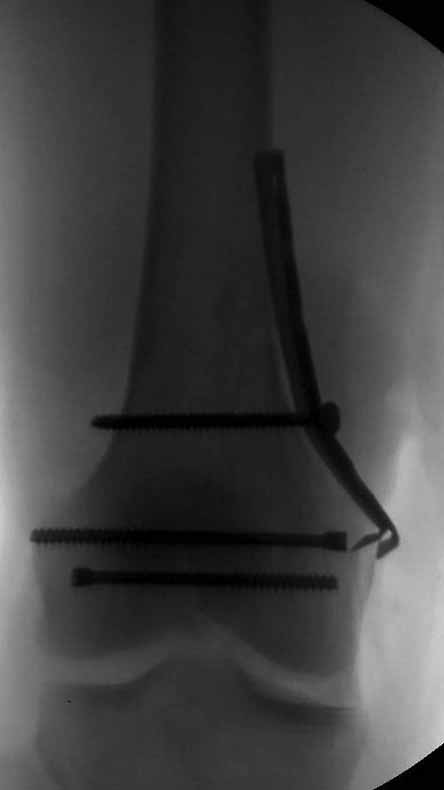

Ну зачем же так. Всё-таки считается "золотым стандартом". Во вложенном файле коллаж из сохранившихся фотографий одной из операций. Всё сделано закрыто и без ЭОПа.

Ответ на эту часть Вашего поста – вложенный файл. Больная оперирована неделю назад по поводу открытого перелома дистального эпиметафиза бедренной кости. После операции она идёт в рентгенкабинет для выполнения послеоперационной контрольной рентгенографии, представленной на слайдах 10 и 11. Узнав, почему её фотографируют, просила передать Вам, Антон, привет.

В приложении пример недавней операции, C3, открытая репозиция, фиксация мыщелков спицами и винтами, ретроградный синтез большеберцовым гвоздем 10,5 мм диаметром, винты 5 мм.

Коллеги, извиняюсь за задержку с результатом. Через медиальную артротомию обнажили н/3 бедра, отрепонировали внутренний мыщелок, затем по нему сопоставили суставную поверхность бедра с латеральным мыщелком.

Больная выписана в ортезе с регулируемым углом сгибания в колене, с рекомендациями через 3 нед. удалить спицы и начать разрабатывать сустав.

По прямому снимку репозиция удалось, поздравляю! А с латеральной стороны подозрение на флексионный компонент латерального мыщелка остается, а снимок получился косым, надо было бы повторить.

Выбор имплантов не совсем удачный, подкожно выступающие болты в мыщелках вскоре могут привести к проблемам. Вместо солитарной фиксации болтом-стяжкой дистально можно было бы добавить пару винтов, которые создали бы ротационную стабильность и межфрагментарную компрессию.